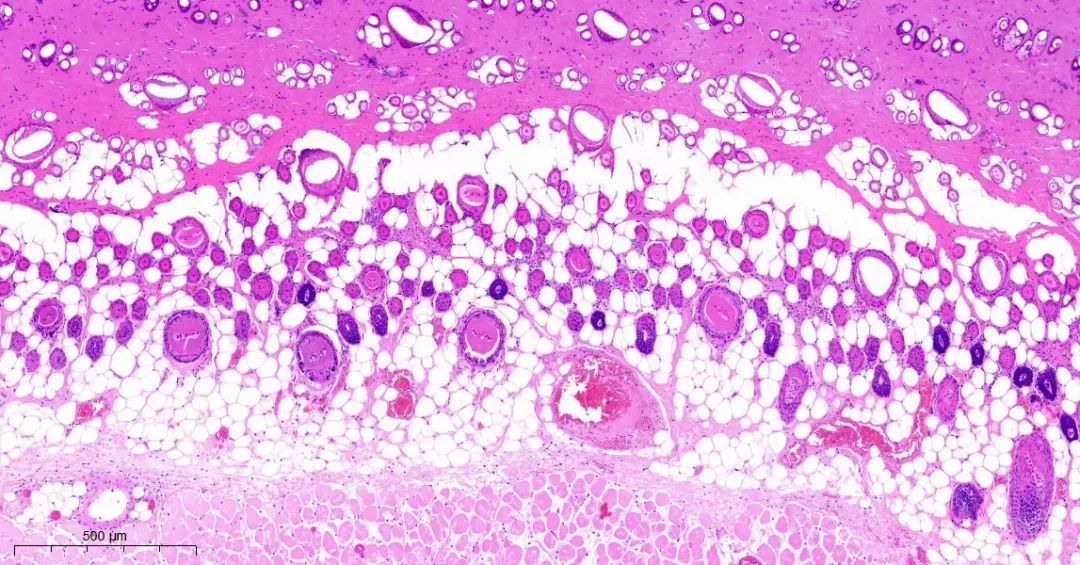

取正常对照组及模型组大鼠背部皮肤标本,常规固定,石蜡切片,HE染色,观察皮肤组织学变化。

模型1组皮组织切片对比

模型2组皮组织切片对比